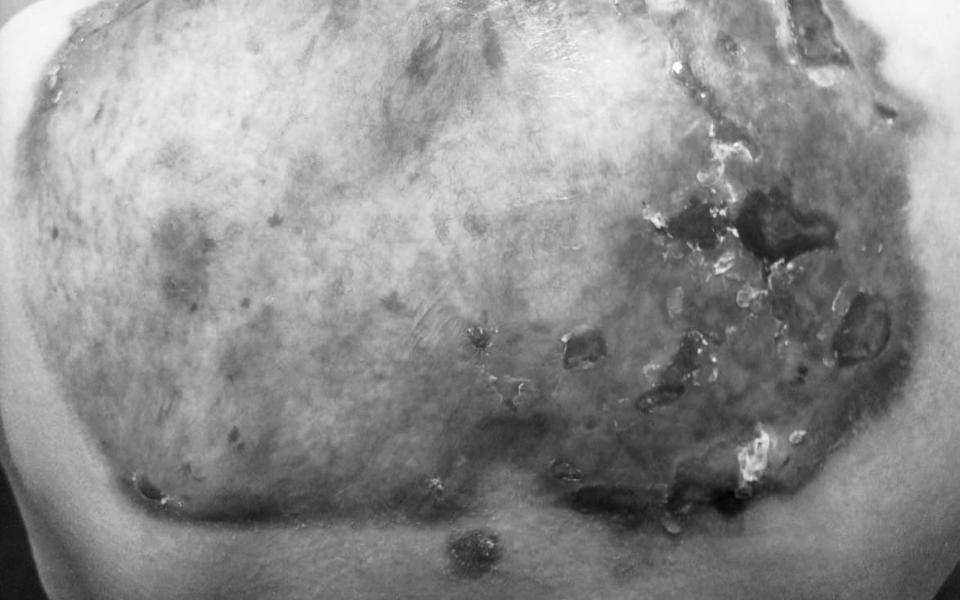

В Рязанском кожно-венерологическом диспансере будут лечить одного из 494 детей в России с заболеванием «буллёзный эпидермолиз», которое ещё называют «болезнь бабочки». Об этом сообщили в пресс-службе регионального минздрава.

Болезнь генетическая и крайне опасная для носителя. Даже слабое механическое воздействие может привести к образованию пузырей на различных областях кожного покрова, а далее образовываются рубцы на месте поражения. Порой это происходит и без какого-либо воздействия, непроизвольно. Рязанские пациент с таким диагнозом с младенчества.

Всего в России детей с подобным диагнозом 494, а в Рязани будут применять лечение впервые. В частности, в медучреждение доставят препарат «Виджувек» для локальной генной терапии ран.